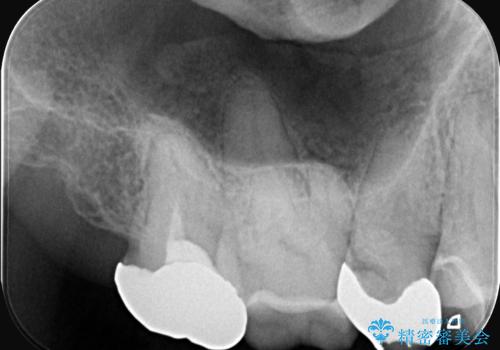

- お口の中にある銀歯を全てなくして、白く健康的な状態にしたい」という主訴でご来院されました。長年使用してきた複数の銀歯は、経年劣化により適合が悪くなっており、一部では内部で二次カリエス(虫歯の再発)も認められました。

銀歯の除去と精密な再治療: 古い銀歯を一つひとつ丁寧に取り外し、内部の虫歯を徹底的に除去。神経を保護するための処置を行った上で、適合性を極限まで高めるために精密な型取りを行いました。

オールセラミックによる修復: 天然歯のような光の透過性と硬さを持つオールセラミックを使用しました。奥歯であっても、患者様固有の歯の色調や咬み合わせの溝を忠実に再現した修復物を装着。金属を一切使用しないことで、金属アレルギーのリスクを排除し、歯肉の色が黒ずむ心配もなくなりました。